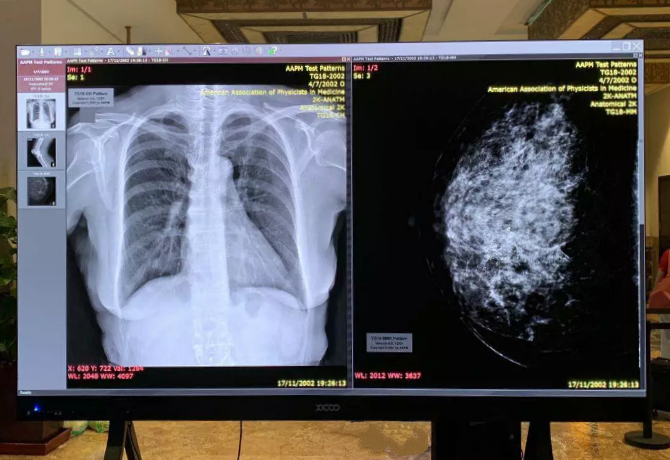

除了“大場景”的智能化應用,希科醫(yī)療同時也推出了“一體化人體工學閱片中心”解決方案,致力于提升放射醫(yī)師的工作體驗,為放射醫(yī)師提供更優(yōu)質(zhì)、舒適和專業(yè)的顯示設備及工作環(huán)境。一體化閱片中心解決方案不僅僅是給放射醫(yī)師提供一個辦公場所,它具備的顯示質(zhì)量管理平臺、醫(yī)生輔助診斷功能、醫(yī)生健康管理系統(tǒng)及膠片自動識別技術,將會給放射醫(yī)師帶來全新的交互體驗和更高效的辦公場景。

一體化人體工學閱片中心